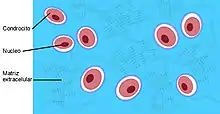

Cartílago articular

Desempeña un papel muy importante en las articulaciones sinoviales como la rodilla y el hombro, está constituido por cartílago hialino y recubre la superficie de los huesos, siendo su espesor entre 2 y 4 mm. Tiene la función de transmitir y amortiguar las cargas y proporcionar una superficie adecuada para el deslizamiento de las superficies articulares. No tiene vasos sanguíneos propios, por lo que las sustancias nutritivas le llegan a través del líquido sinovial. La capacidad de regeneración si sufre lesiones o desgaste por sobrecarga es escasa.[5] Está compuesto por células especiales llamadas condrocitos rodeados de matriz extracelular. La matriz extracelular está formada por agua (65-80 %), colágeno (10-20 %) y proteoglicanos (10-15 %) que le otorga resistencia a las fuerzas de compresión. Los condrocitos son las encargadas de producir los componentes estructurales que forman el cartílago.[5][6]